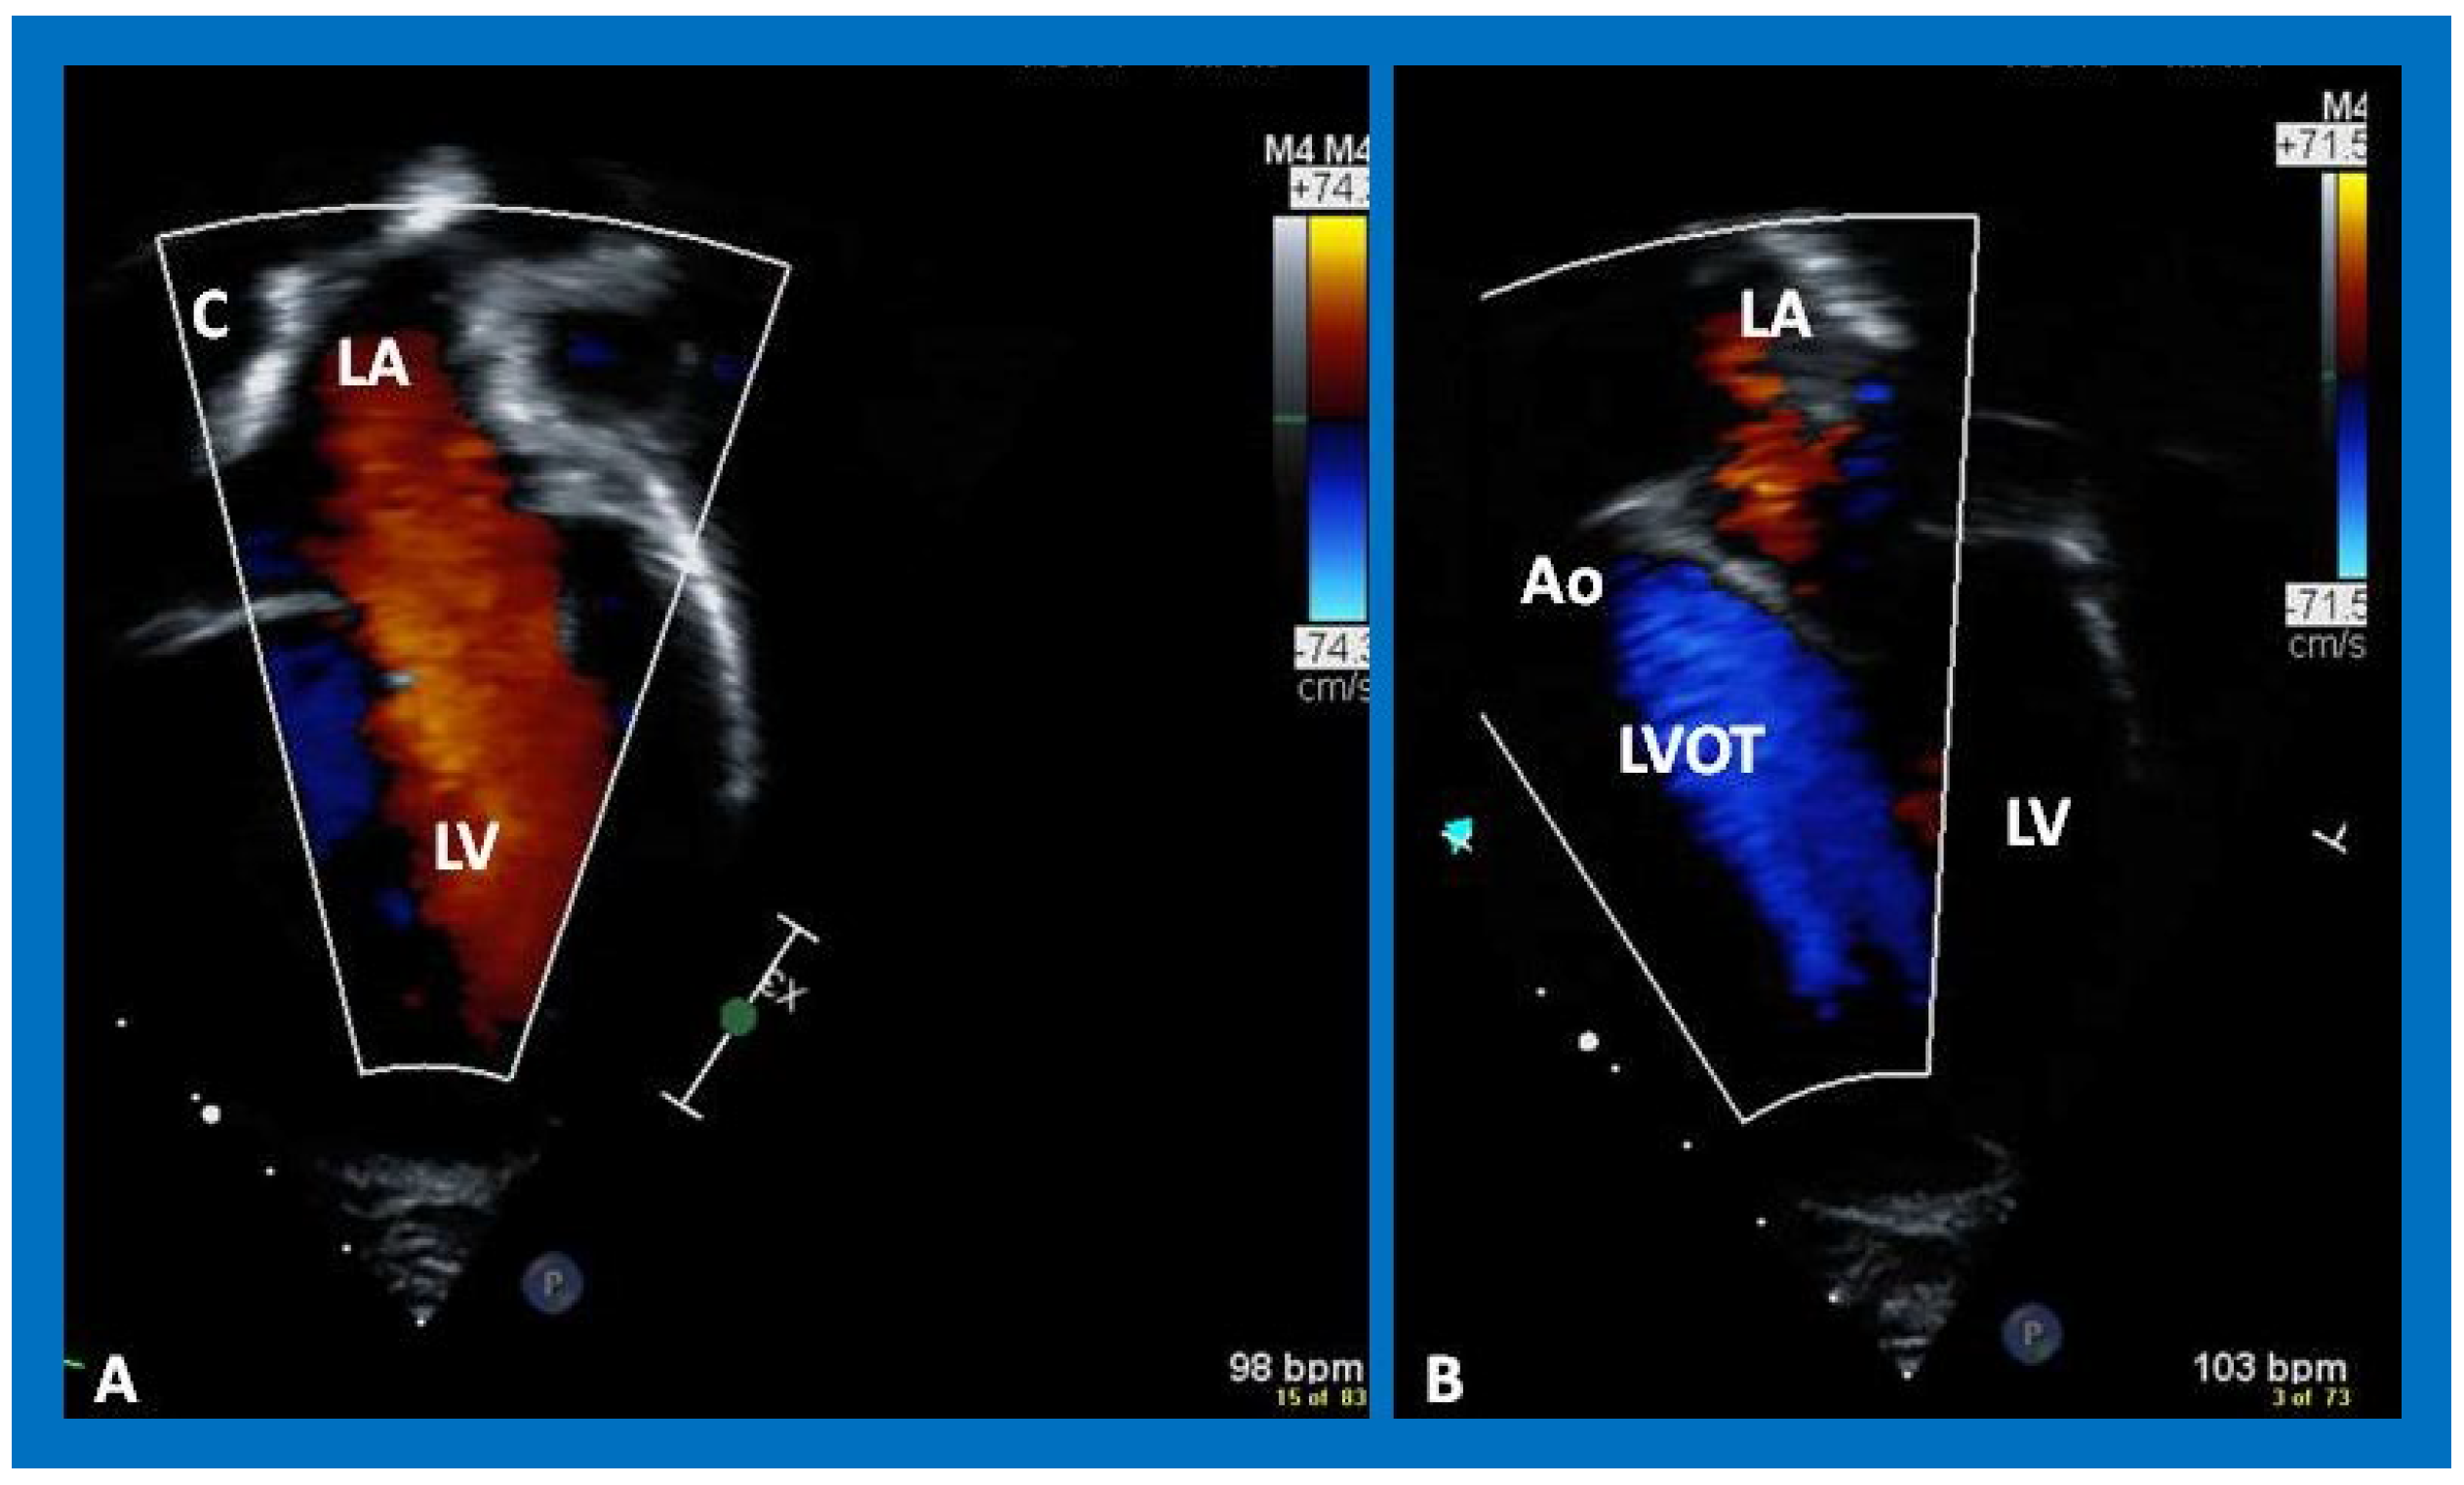

Post-Fontan echocardiographic anatomy is best displayed in apical four chamber views, as demonstrated in Figure 38, Figure 39 and Figure 40. The remnants of the RA and the LA are seen (Figure 38, Figure 39 and Figure 40). The remnants of atrial septum are not usually seen since the atrial septum is completely removed either during bidirectional Glenn or Fontan surgery. Unobstructed pathway allowing emptying of blood flow from the coronary sinus and thebesian veins is usually seen in an apical four chamber view (Figure 40).

The LA is usually normal in size (Figure 38, Figure 39 and Figure 40) and empties into the LV; laminar flow across the mitral valve (Figure 41A) can be seen. Drainage of all four pulmonary veins into the LA may be demonstrated by color flow mapping in multiple echocardiographic views. The LV is either normal in size or slightly dilated. In type I patients with normally related great arteries, the LV outflow into the aorta is demonstrable on echo-Doppler with laminar, unobstructed flow with near normal (~1.0 m/s) Doppler flow velocity (Figure 41B and Figure 42). The RV is small and hypoplastic (Figure 39 and Figure 40). If the VSD has already spontaneously closed (Figure 40), the RV has no communication with any other structures since the connection with the PAs has been severed during bidirectional Glenn or Fontan procedures. If the VSD did not undergo spontaneous closure, the RV forms a cul-de-sac connection with the LV (Figure 39 and Figure 43). In Type I patients with atresia of both tricuspid and pulmonary valves (Type Ia), the hypertrophied RV may protrude into the LV outflow region (Figure 44). However, there is usually no evidence for obstruction across this region (Figure 45).

Figure 41. Selected video frames from an apical views demonstrating laminar flow from the left atrium (LA) to the left ventricle (LV) (A) and from the LV to aorta (Ao) (B). Note laminar flow in the LV outflow tract (LVOT) (B). Medial portion of the conduit (C) is seen in (A).